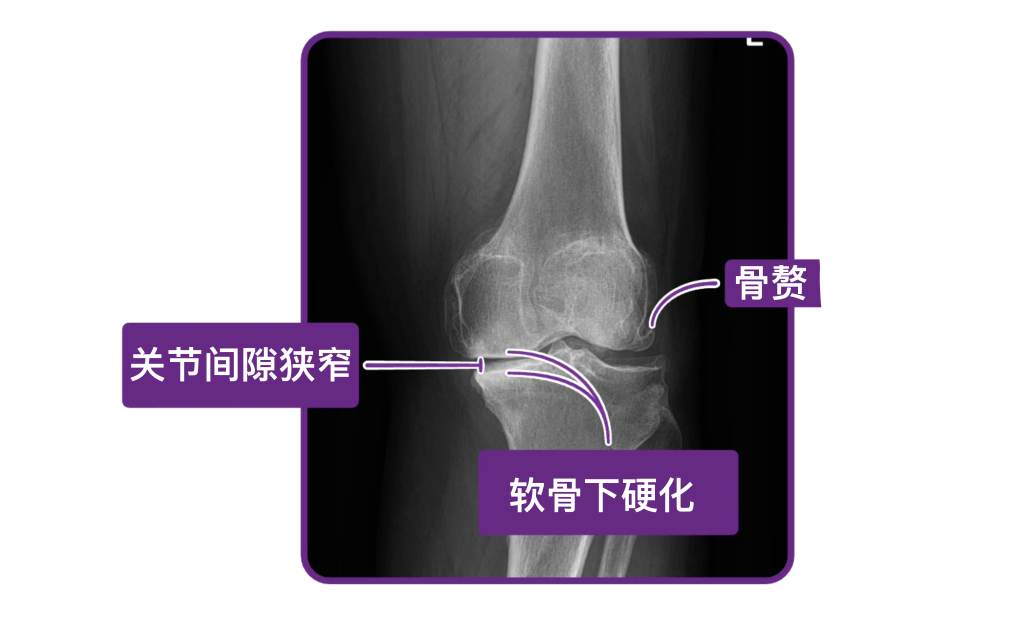

如果病史和体格检查结果与骨关节炎一致,则无需进一步检查,即可做出骨关节炎的诊断。但如果诊断不明确,就应为受累关节拍摄X线片。如果X线结果与骨关节炎不符,就要考虑其他诊断。相反,如果X线显示关节间隙变窄、骨赘形成以及软骨下硬化,就可以诊断为骨关节炎。

这里有一个临床要点:在骨关节炎患者中,X线所见与临床症状并不总是相符。例如,X线可能提示关节严重损伤,但患者可能只表现出轻微的症状。